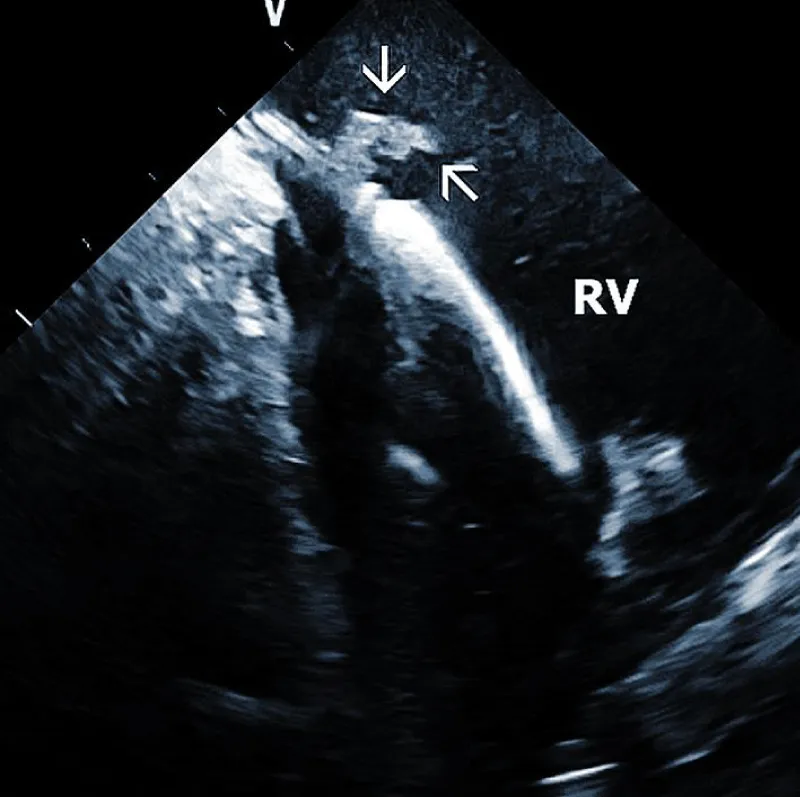

Lead adherent echo densities (LAE): ICE allows visuali-zation of the leads and echo densities adherent to them. In our experience, LAE can be detected in the majority of patients (Figure 2A). One recent study revealed LAE in 72% of cases [10]. Locations of LAE were the superior vena cava (16%), its junction with the right atrium (11%), right atrium (57%), and tricuspid annulus (16%). Finding LAE opens the question of their clinical importance. Interestingly, Ho, et al. systematically performed TEE before TLE, which was performed for non-infectious indications in 108 consecutive patients [11]. The authors reported an 18.5% incidence of lead thrombi, all of which were < 2 cm. This figure is significantly less than in the above study. This discrepancy can be explained by the higher resolution and superior maneuverability of ICE compared to TEE [12].

Figure 2A: Depiction of the lead adherent echodensity (arrows) floating on the ICD lead in the right ventricle (RV).

Therefore, ICE could be essential in patients with a suspected diagnosis of infective endocarditis since it necessitates the removal of the entire pacemaker or ICD system. Narducci et compared ICE with TEE to detect TLE in the setting-related infective endocarditis [13]. ICE identified the presence of intracardiac masses in all 58 patients (100%), whereas TEE identified the presence of ICM in only 38 patients (65%). The authors concluded that ICE is a useful technique for diagnosing intracardiac masses, thus providing improved imaging of right-sided leads and increasing the diagnostic yield compared with TEE. The pretest probability of infective endocarditis determines the incremental diagnostic value of ICE in infection of implantable devices. If the diagnosis of endocarditis is clinically rejected, even ICE does not improve the clinical decision-making process. The best diagnostic value of ICE was found in patients with a probable diagnosis of endocarditis. We recently had an ongoing pilot project focused on biopsies from TLE using a bioptome and ICE guidance. In anecdotal cases, it helped to establish the diagnosis of infective endocarditis.

Technically speaking, the presence and size of intracardiac masses in patients suspected of infective endocarditis are critical in planning TLE procedure (Figure 2B). Large vegetations were found more common in patients with renal failure, heart failure, ICD system, and loops of the leads [14]. In another study, diabetes was related to larger vegetations, similarly younger age. Anticoagulation therapy resulted in smaller vegetations [15].

Figure 2B: Large vegetation floating on the ICD lead in the Right Atrium (RA). RV: Right Ventricle.